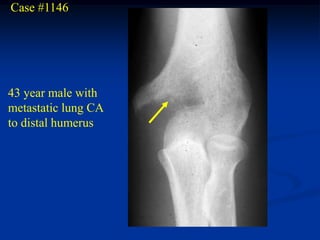

Case #1146

43 year male with

metastatic lung CA

to distal humerus

Lateral view

Chest x-ray showing primary lung CA right apex